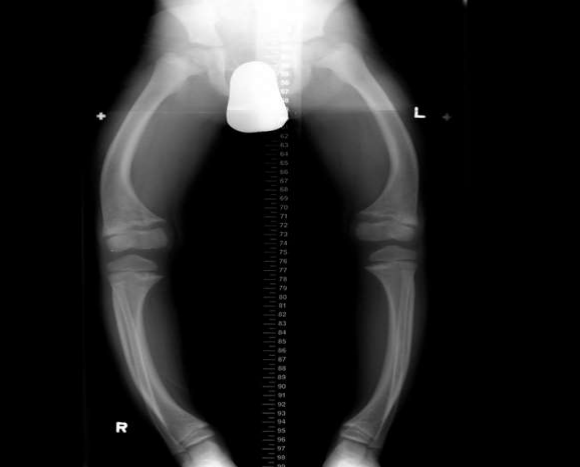

Measurements can be made in the supine or standing position from the superior iliac crest to the medial malleolus using a tape measure or block test. Move your legs up to the level of the iliac crest and then measure the size of the block to determine the difference. The reason for the length difference. It develops soon after most children start walking. Although most children are asymptomatic, parents often report that their child frequently falls or trips. . However, genu varum does not seem to indicate Blount disease in children younger than 18 months unless the overall deformity is severe or very close to the tibial angle comfort. The most accurate method is longitudinal (hip to ankle) radiography, radiography scan, or computed tomography (CT). your ruler. CT scans can be used in a similar way but can also evaluate limb stiffness and movement. There are also new imaging techniques using low-energy imaging that can provide body length measurements with less energy than XR (EOS imaging). Bone age should also be evaluated to determine the prognosis for growth.

Figure 4: Bottom X-rays are X-rays obtained by placing a probe and moving the beam to the right over each image. The screening usually includes both legs of the film.